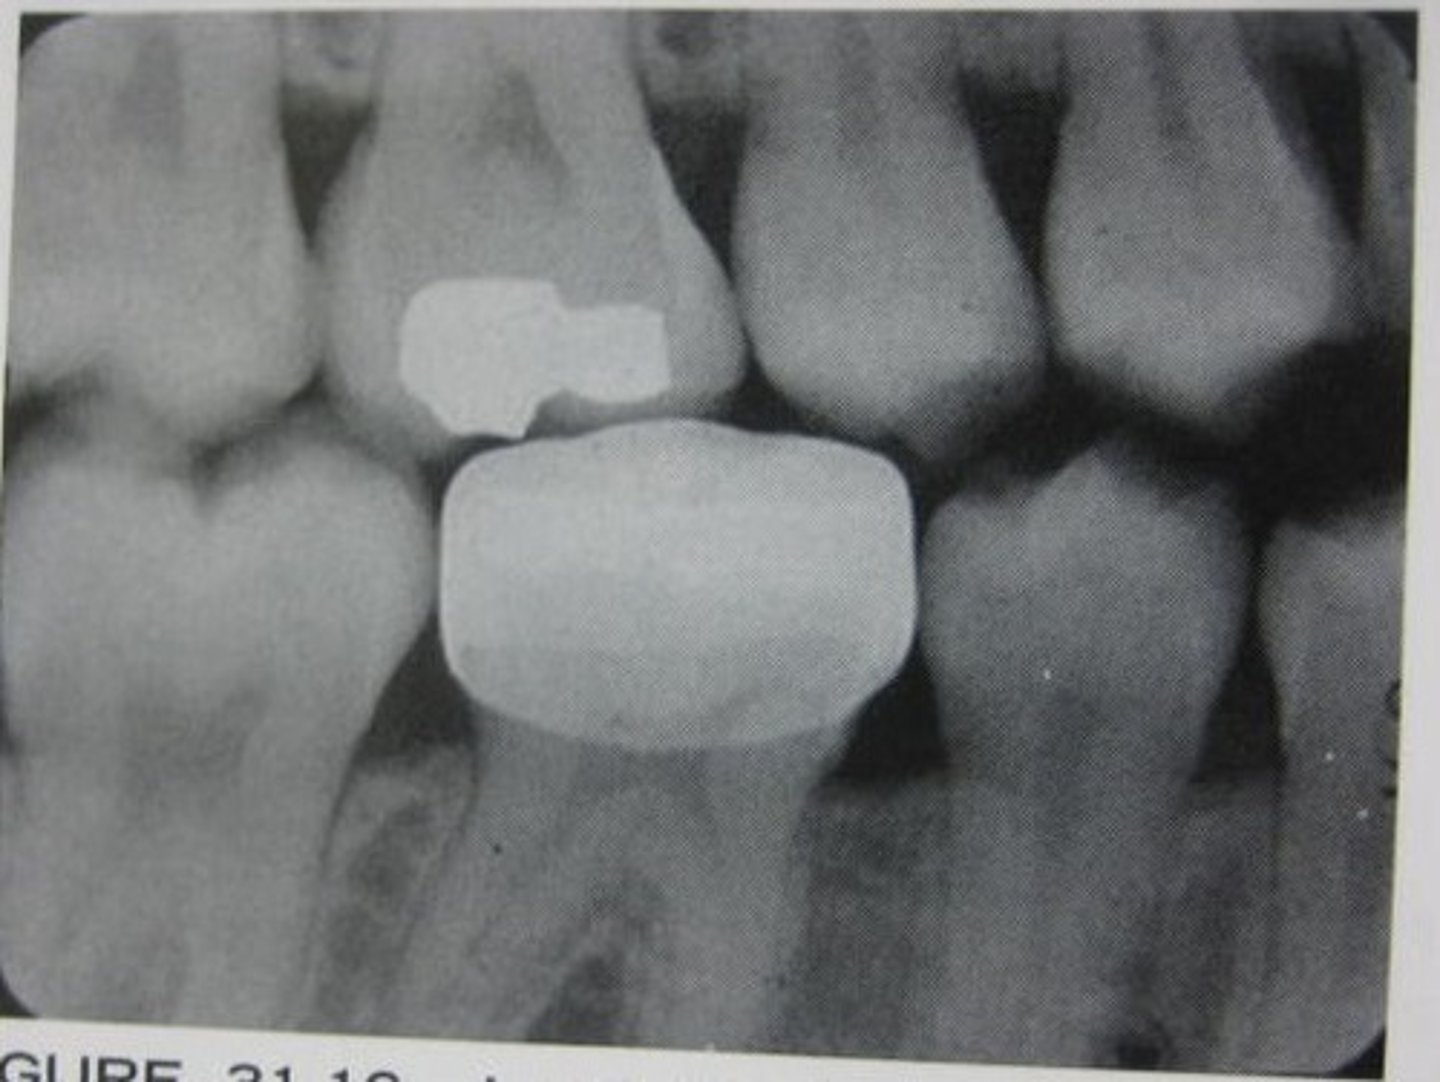

MOD amalgam

overhang

PINS